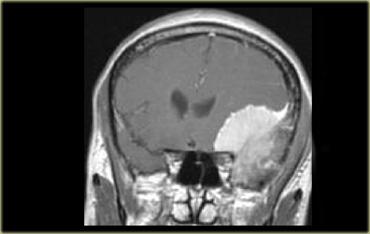

Chuỗi xung T1W có thuốc tương phản từ, mặt phẳng coronal. U màng não với dấu hiệu đuôi màng cứng, tăng sinh xương lân cận và ngấm thuốc đồng nhất

Một dấu hiệu khác của nguồn gốc ngoài trục là nền màng cứng rộng hoặc dấu hiệu đuôi màng cứng ngấm thuốc, thường thấy điển hình trong u màng não.

Dấu hiệu này cũng có thể gặp ở các u ngoài trục khác, nhưng ít phổ biến hơn.

Một dấu hiệu khác của nguồn gốc ngoài trục là các thay đổi ở xương.

Thay đổi xương được thấy trong các u xương như u dây sống (chordoma), u sụn ác tính (chondrosarcoma) và di căn xương.

Chúng cũng có thể là thứ phát, như thấy trong u màng não và các u khác.

Bên trái là ví dụ về u màng não với nền màng cứng rộng và dấu hiệu đuôi màng cứng ngấm thuốc.

Có tình trạng tăng sinh xương ở xương lân cận và tổn thương ngấm thuốc đồng nhất.

Các u ngoài trục không có nguồn gốc từ mô não và không có hàng rào máu não, do đó hầu hết chúng ngấm thuốc đồng nhất.